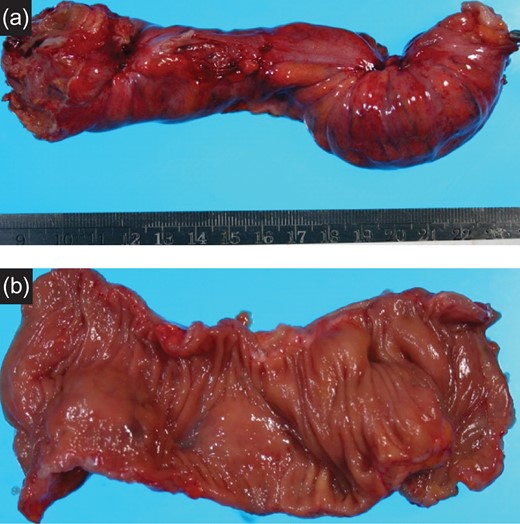

Specimen: Strong dimpling of the serosa on rectum and ileocecum was recognized (Figs 3a, b and 4a, b).

(a) Resected specimen (rectum): The serosal dimpling was observed. (b) Resected specimen (rectum): A SMT-like lesion was observed.

(a) Resected specimen (ileocecum): Serosal dimpling was also observed. (b) Resected specimen (ileocecum): A SMT-like lesion was also observed.

Pathological findings: Fibrosis and the ecchymosis were pathologically observed. Endometrial tissue was seen at the muscular layer indicated ecchymosis. There were no malignant cells or lymph node metastasis (Fig. 5a, b).